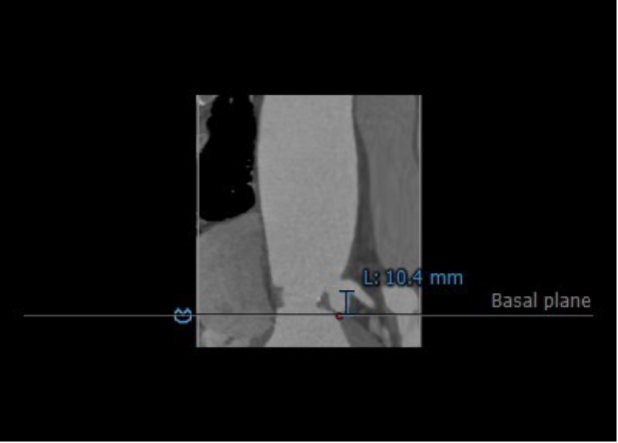

3.患者双侧冠脉开口高度尚可:LCA:10.4mm,RCA:13.3mm。

左冠开口高度:10.4mm